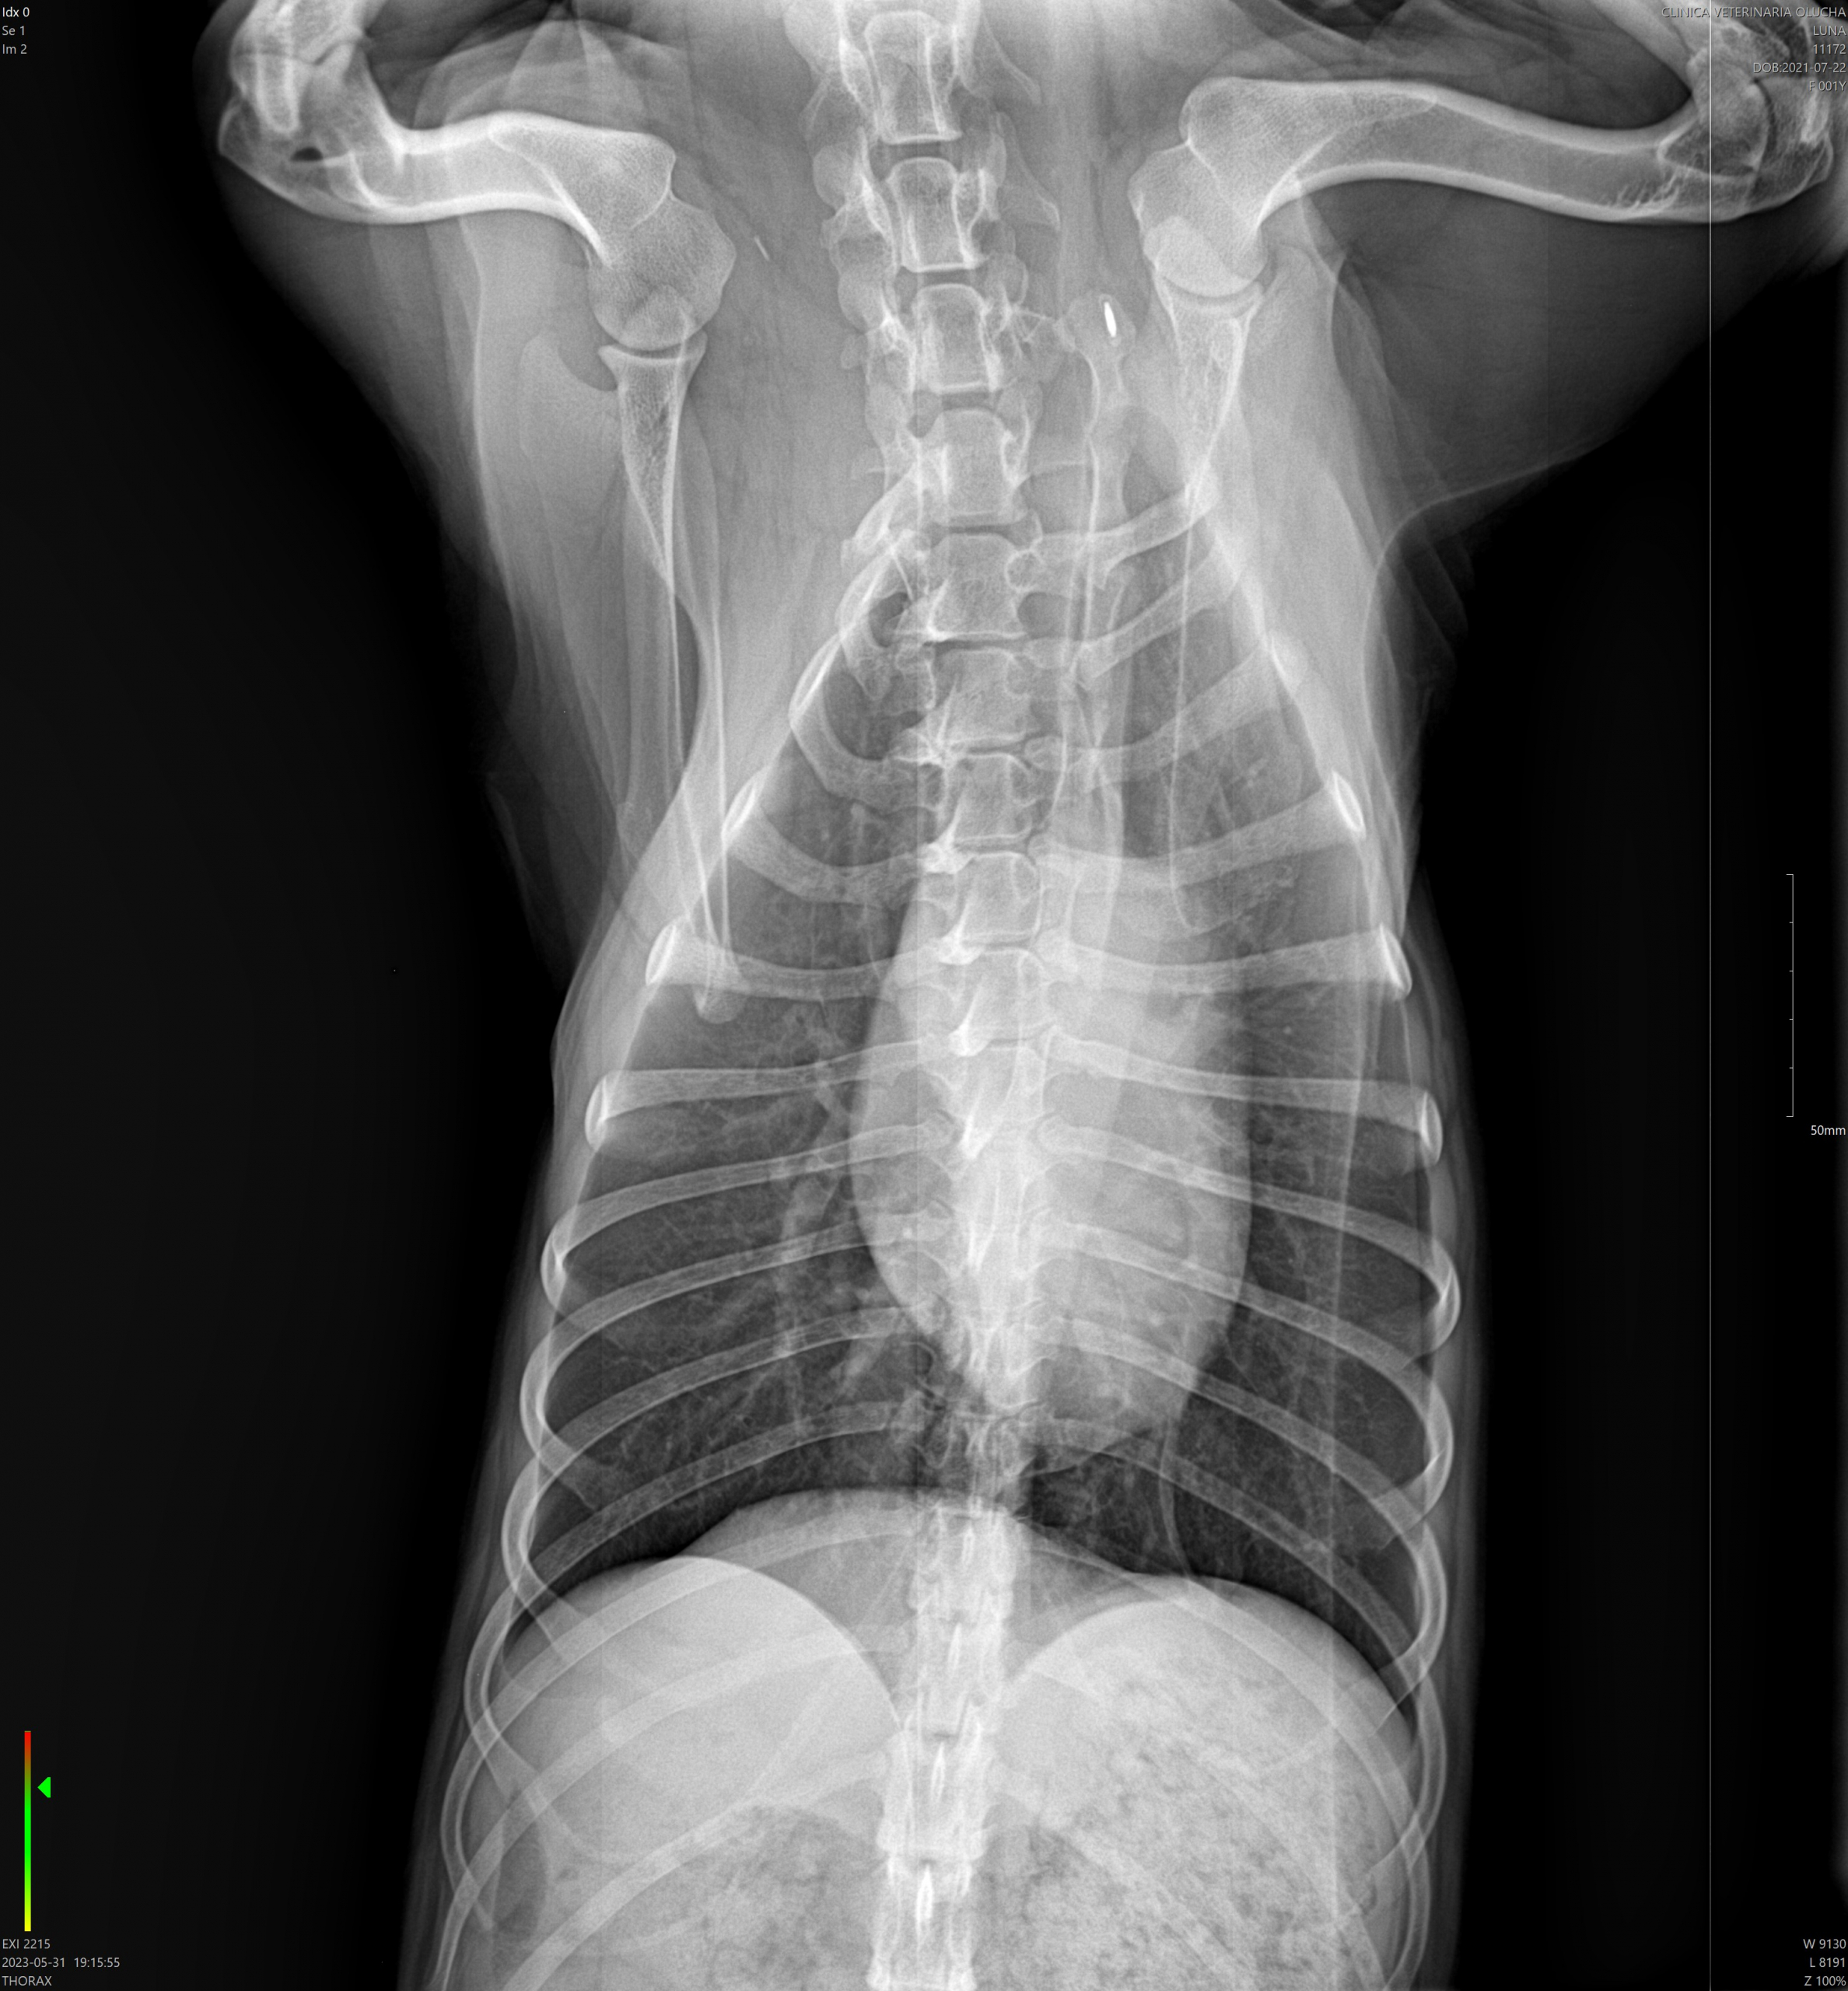

La radiología veterinaria es una herramienta fundamental dentro del diagnóstico por imagen y desempeña un papel clave en la detección, evaluación y seguimiento de múltiples patologías en perros y gatos. En Clínica Veterinaria La Graveta, contamos con radiología digital de alta calidad, que nos permite obtener imágenes nítidas y precisas de forma rápida, segura y con una mínima exposición a la radiación.

Gracias a la radiología veterinaria podemos evaluar de manera eficaz huesos, articulaciones, columna vertebral y órganos internos, facilitando un diagnóstico temprano y una correcta planificación del tratamiento más adecuado para cada paciente. Esta técnica es especialmente útil en casos de traumatismos, cojeras, problemas articulares, alteraciones óseas, enfermedades respiratorias, digestivas o cardiacas, así como en el control de procesos crónicos.